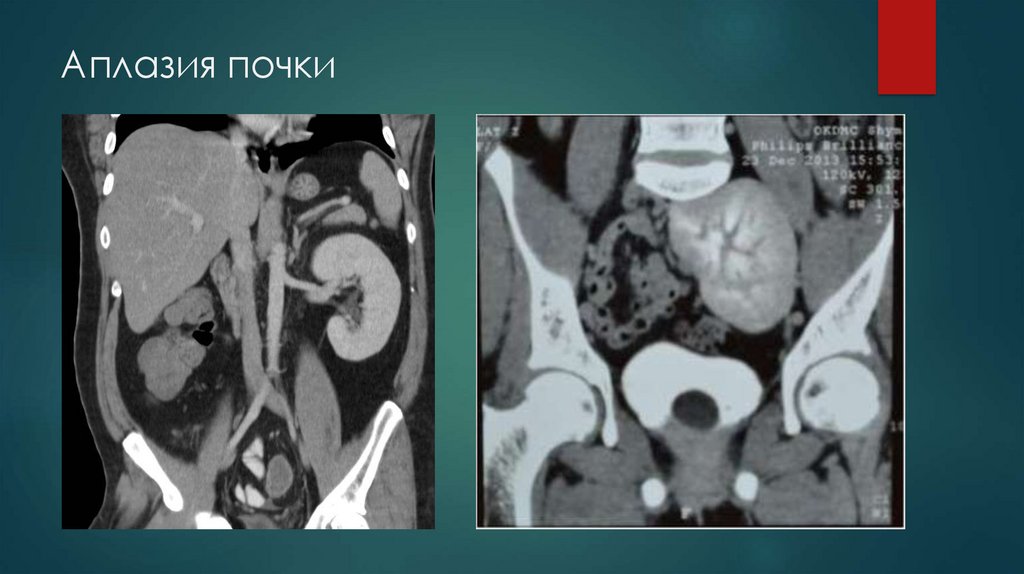

Аплазия почки

- Аплазия